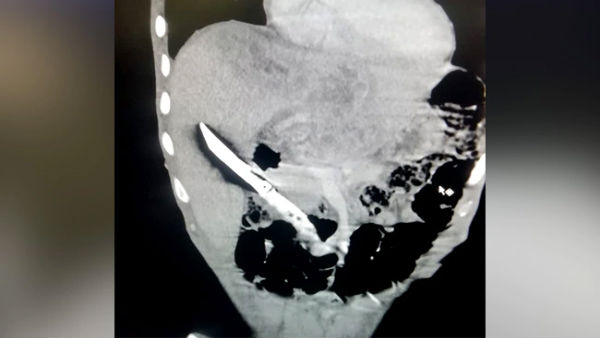

Rare surgery: 20-cm knife removed from 28-year-old man’s liver

New Delhi, Jul 27: After a rare and challenging three-hour surgery, doctors at the AIIMS here successfully removed a 20-cm-long kitchen knife from a man's liver who had bizarrely swallowed it in a fit of psychosis. The doctors said they were perplexed as to how the 28-year-old gulped down the saw-edged knife without any damage being caused to his wind-pipe, lungs, heart and other vital organs.

"An ultrasound and an X-ray of the abdomen revealed blade of a kitchen knife stuck in the liver. Anticipating the challenges involved in removing the object, doctors there referred the patient to the Gastrointestinal Surgery and Liver Transplant department at AIIMS," Dr Dash said.

The reports came out negative. While the patient was admitted in the emergency, an ultrasound, CT scan and other investigations were carried out to know the exact position of the knife, its relation to the vital organs and the complications it had caused, the doctors said.

"On CT scan, we found the blade of the knife was entirely inside the liver and the handle inside the duodenum, which is the first part of the small intestine. "The knife actually had perforated the duodenum and had gone into the liver. It had led to bleeding, infection, abscess formation in the liver and sepsis. His hemoglobin level was very low. A sepsis had set in, there was loss of weight and water had accumulated in his right chest," Dr Dash elaborated.